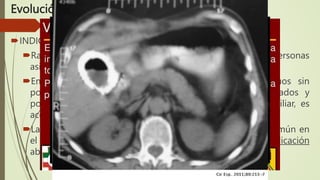

Tomografía computarizada

Los estudios de CT de abdomen son inferiores a la ecografía para el

diagnóstico de cálculos biliares. La principal aplicación de la CT es

definir el curso y estado del árbol biliar extrahepático y estructuras

adyacentes.